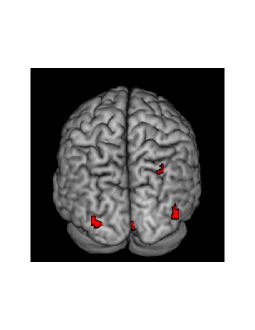

To quantify how much impact the observed difference will have on inference, we create a plot of sensitivity and posterior probability maps (PPM) on the effect of fame (one of the experimental conditions). We do this by first defining a contrast vector . We multiply this vector by , where denotes the vector of regression coefficients at a given voxel, to get a contrast (or effect size) . We note that this contrast measures the effect of fame in the experiment at a given voxel. The posterior distribution of the contrast is then shown across voxels using a PPM. This map is based on two thresholds, the first being an effect size threshold and the other being a probability threshold . The value of is set to a constant so that top of the values across voxels of are considered as ”activated”. The value of the probability threshold is set to be . At each voxel we then compute, using the posterior distribution,

| (29) |

and we highlight those voxels where the posterior probability is greater than . The PPM’s obtained from HMC and VB, together with the sensitivity plot showing the true positives of fame, are depicted in Figure 5. Examining this figure we note that there is a lack of power exhibited by both methods. Type 2 error is a problem in neuroimaging analysis in general but it is important to keep in mind that this is a difficult low SNR setting. From the figure, we see that HMC can capture about 15% of the simulated activations at a probability threshold of , while VB is unable to capture any of the activations. Overall, we see that in a low SNR setup the performance of VB is relatively poor when compared with HMC.